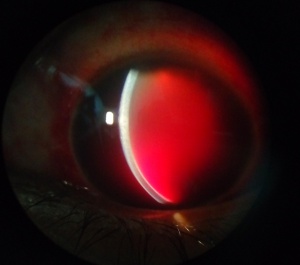

A hyphema is the accumulation of red blood cells within the anterior chamber. A small amount of blood that is only evident under close microscopic examination is referred to as a microhyphema. A majority of patients present with a history that correlates to the etiology. The most common risk factors are a history of trauma or recent ocular surgery. However, a seemingly spontaneous hyphema can result at times from other causes. Despite the degree or etiology, the management of a hyphema and its associated complications can be challenging for any ophthalmologist.

Diagnosis is made with slit-lamp examination of the anterior chamber. A large hyphema can be noted with pen-light examination alone.

Signs

A large hyphema can be noted with pen-light examination alone. The height and color of the hyphema should be documented. Height can be measured in millimeters from the inferior corneal limbus. Color can vary from red to black depending on the time frame of the hyphema. Blood that has clotted will appear darker in appearance (black). It is important to evaluate intraocular pressure.

Hyphemas can be graded in the following manner:[4]

- Grade 0: There is no visible layering, but there are red blood cells within the anterior chamber (microhyphema).

- Grade I: Layered blood occupies less than one-third of the anterior chamber.

- Grade II: Blood fills one-third to one-half of the anterior chamber.

- Grade III: Layered blood fills one-half to less than total of the anterior chamber.

- Grade IV: There is total filling of the anterior chamber with blood. If the anterior chamber is completely filled with bright red blood, it is called a total hyphema. If the anterior chamber is filled with dark red-black blood, it is called a blackball or 8-ball hyphema. The black color is suggestive of impaired aqueous circulation and decreased oxygen concentration. This distinction is important because an 8-ball hyphema is more likely to cause pupillary block and secondary angle closure.[6]

All images are provided courtesy of the Krieger Eye Institute (KEI) at Sinai Hospital of Baltimore, along with Dr. Gregory Oldham.